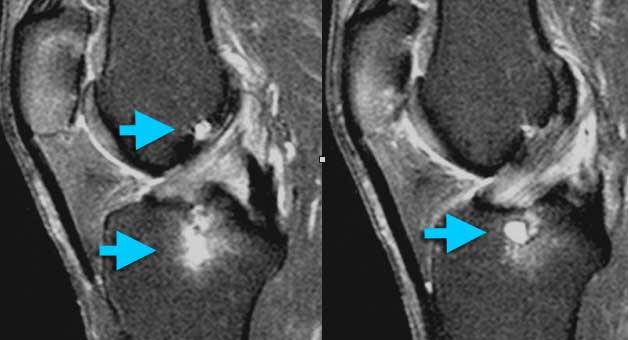

Viêm xương sụn bóc tách

Chẩn đoán Viêm xương sụn bóc tách thường được thực hiện trên X-quang.

Câu hỏi đặt ra khi chụp MRI là tổn thương ổn định hay không ổn định.

Ca lâm sàng bên trái là không ổn định vì hai lý do:

– Các nang nhỏ ở nền tổn thương (mũi tên đỏ)

– Quan trọng hơn là có dịch ở nền tổn thương (mũi tên xanh)

Lưu ý rằng lớp dịch này khác với AVN, nơi dịch nằm giữa sụn và xương.

Viêm xương sụn bóc tách không ổn định. Dấu hiệu duy nhất có giá trị để chẩn đoán OD không ổn định là dịch (mũi tên vàng), không phải phù tủy hay gián đoạn bề mặt xương sụn (mũi tên xanh lá).

Các dấu hiệu không có giá trị trong việc phân biệt OD ổn định và không ổn định bao gồm:

– Phù tủy xương (có thể gặp trong cả hai trường hợp)

– Gián đoạn bề mặt xương sụn.

Vì vậy, ca lâm sàng bên trái là không ổn định vì có dịch ở nền tổn thương.

Ca lâm sàng bên trái cho thấy viêm xương sụn bóc tách với phù tủy xương và gián đoạn bề mặt xương sụn.

Tuy nhiên, vì không có dịch, chúng ta không thể xác định đây là tổn thương ổn định hay không ổn định.

Trong phẫu thuật, tổn thương viêm xương sụn bóc tách được xác nhận là ổn định.

Trong những trường hợp không thể xác định tổn thương ổn định hay không ổn định, chụp MRI khớp có thuốc tương phản từ (MR-arthrogram) rất có giá trị.

Chúng ta tìm kiếm dấu hiệu Gadolinium thấm vào xung quanh tổn thương xương sụn.